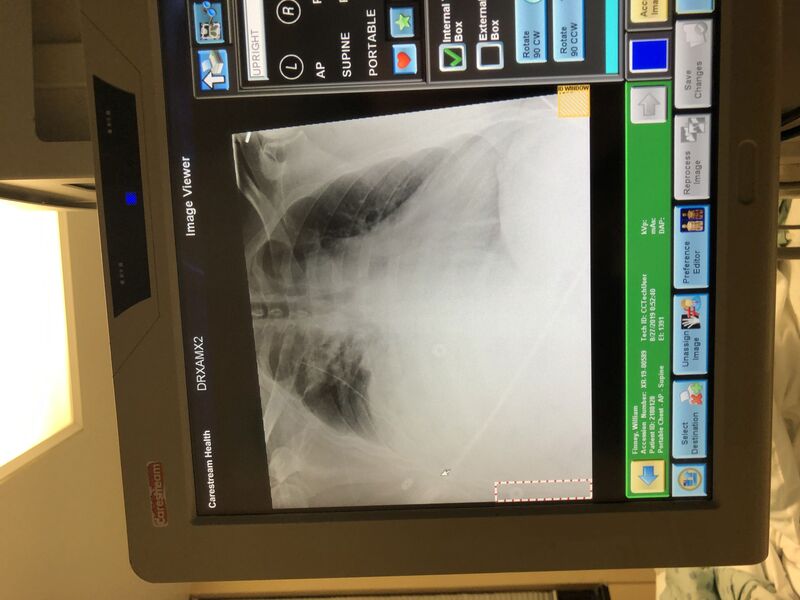

Blood in lung Lung tube Lung blood box

Now that I had a suction tube in my lungs, we have to watch the amount of blood being removed. We watch my "lung blood box", as I called it, and the x-rays to monitor my status. Tuesday afternoon a surgeon paid me a visit. He gave the hard truth. The suction is only going to remove so much. If we don't get enough blood out of my right lung I will have to have surgery to scrape it out.

There was a way to get more blood out of the suction tube. I could breathe deep and cough hard to shake things up. There was a challenge to those two activities, especially the coughing. It was extremely uncomfortable. I felt a sharp pain and I felt tremendous amounts of pressure. Kenny and Dr Jones had educated me that pressure was ok. I could and must push through the pressure. My brain however was freaking out at the unfamiliar sensations.

Chest x-ray looks great surgeon said fluid looks to have gone out and change to water seal instead of suction—-surgeon said all his work is paying off and very pleased. Surgery not out of possibility until tube is out but he's super happy with where he's heading